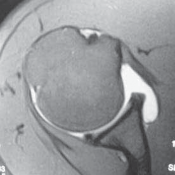

19. MRI can identify intratendinous tendon abnormality, bicipital sheath hypertrophy, concomitant superior labral and rotator cuff pathology, the intra-articular course of the tendon, and the relationship of the biceps to the structures of the annular reflection pulley that stabilize it (

FIG 3

).

FIG 3 • Coronal MR image showing a normal-appearing biceps tendon in the bicipital groove adjacent to a normal subscapularis tendon and overlying annular reflection pulley.